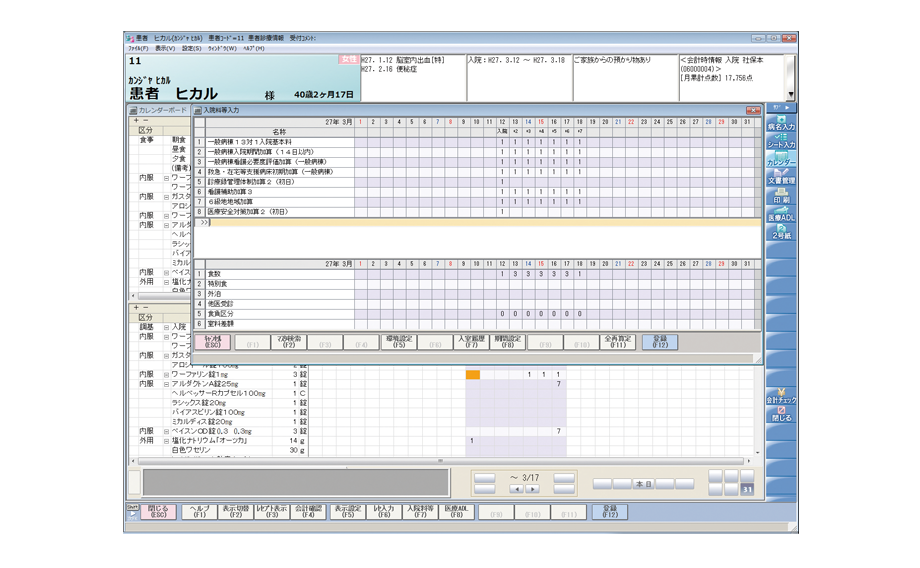

入院専用画面で、入院患者の情報を一元管理します。

入院受付や入院会計にも対応し、入院事務もスピーディーに処理します。